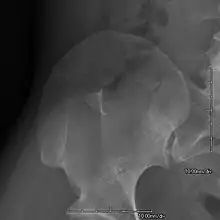

- Exostoses arising from the posterior aspect of the iliac bones ("iliac horns") are present in as many as 80% of patients; this finding is considered pathognomonic for the syndrome.

This is a view from a different angle of the same man's other elbow